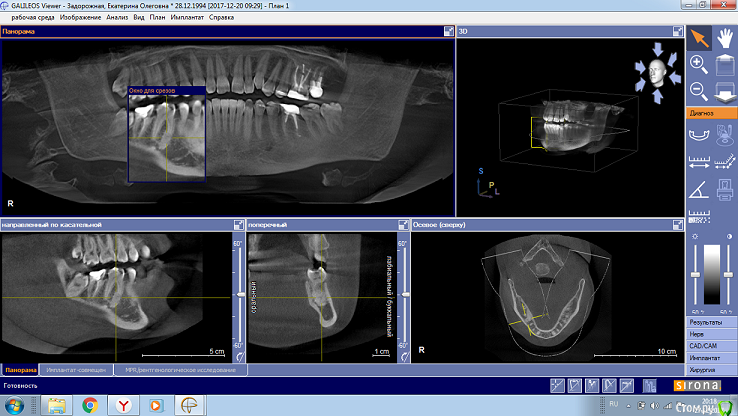

kat_zadorozhnaya Опубликовано 27 декабря, 2017 Поделиться Опубликовано 27 декабря, 2017 (изменено) Добрый День! Пришла 8 дней назад пришла в стоматологию лечить 6й зуб, т.к. иногда побаливает и под пломбой кариес. Исходя из рентгеновского снимка врач отправил на КТ. По итогам КТ консультация хирурга. Сегодня была, предположил остеому и зуб предложил либо просто пролечить, если не поможет - удалить вместе с остеомой. Ваши предположения? Как быть? Что лечить, что нет, что удалять, а что нет. Гистология?Ссылки ниже. Спасибо Изменено 27 декабря, 2017 пользователем kat_zadorozhnaya Ссылка на комментарий

red_butler Опубликовано 27 декабря, 2017 Поделиться Опубликовано 27 декабря, 2017 а на что больше похоже данное новообразование? Я очень беспокоюсь, т.к. не знаю как давно оно там, рентген данного зуба никогда не делала. Врач, конечно, сказал, что я не первый год живу с этим, и всю жизнь с этим люди живут. Участок остеосклероза Ссылка на комментарий

DmitrySH Опубликовано 27 декабря, 2017 Поделиться Опубликовано 27 декабря, 2017 Плохого ничего нет? Как прикрепить полноразмерные фото? я бы загрузила, для лучшего качества фото. Лечите как обычный зуб, через год КТ повторить и сравнить. Ссылка на комментарий

St. Опубликовано 27 декабря, 2017 Поделиться Опубликовано 27 декабря, 2017 Сравнить растёт или нет? И потом удалять всё равно?Сравнить уменьшается или нет. В большинстве случаев стандартного лечения каналов достаточно чтобы обойтись без удаления зуба Ссылка на комментарий

kat_zadorozhnaya Опубликовано 28 декабря, 2017 Автор Поделиться Опубликовано 28 декабря, 2017 (изменено) Вылечить зуб чтоб не болел А с белым пятном ниже? Жизни не угрожает? Изменено 28 декабря, 2017 пользователем kat_zadorozhnaya Ссылка на комментарий

DmitrySH Опубликовано 28 декабря, 2017 Поделиться Опубликовано 28 декабря, 2017 Нет, не угрожает Ссылка на комментарий

kat_zadorozhnaya Опубликовано 14 февраля, 2018 Автор Поделиться Опубликовано 14 февраля, 2018 Уважаемые доктора, здравствуйте ещё раз! Выше есть ссылки на фото моей КТ. На что больше похоже данное образование? Пошла лечить зуб, врача смущает, что неровные контуры..Что делать, как быть? Остеома, цементома, склероз? Я очень переживаю. Посмотрите, пожалуйста, ещё разок. Спасибо Вам заранее! Ссылка на комментарий